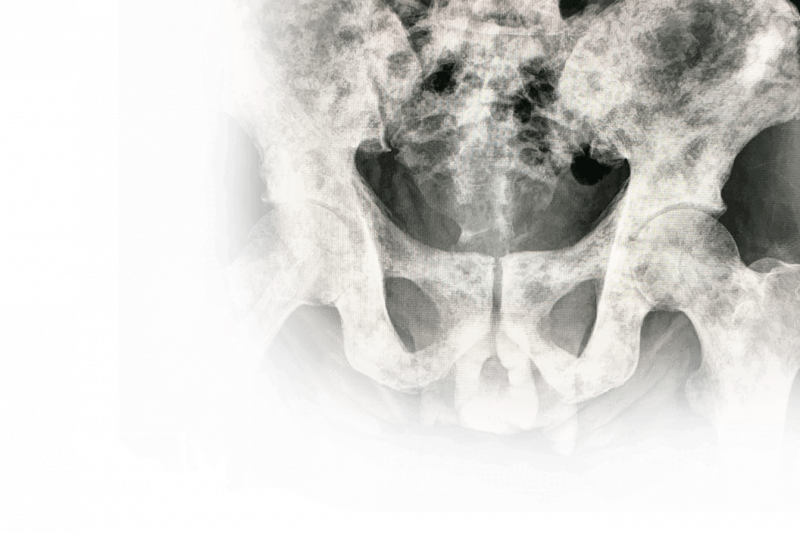

Câncer Ósseo

Imagem de Câncer Ósseo

Câncer nos ossos ocorrem em maior número, em crianças, adolescentes e adultos jovens com idade até 30 anos. É na infância que os tumores se apresentam mais agressivos e as lesões são mais comuns na região do joelho, perto do fêmur e da tíbia.